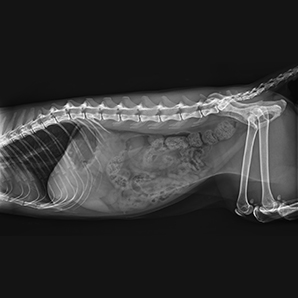

Built on advanced technology in the whole imaging chain, the system delivers a low-dose imaging experience with outstanding image quality for any type of pet. It allows you to finish the exposure with the panel on the tube head, simple operation and instant imaging enable it to use in an easy and fast way for every situation.

Get a high-quality instant image

Instant images on the tube head allow faster diagnoses and enable better communication with animal owners intuitively and clearly.

The four-way tabletop with a large load-bearing capacity can accommodate different kinds of animals, even those with huge shapes.